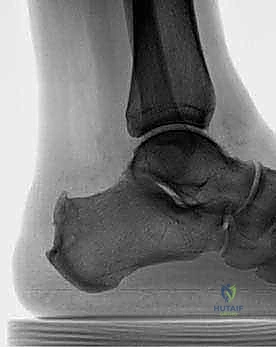

- الأشعة السينية (X-rays): ضرورية لرؤية تكلسات الوتر، وحجم النتوء العظمي (تشوه هاغلوند)، وزاوية عظم الكعب.

- التصوير بالرنين المغناطيسي (MRI): هو المعيار الذهبي لتقييم مدى تلف ألياف الوتر، حجم التمزقات الداخلية، ودرجة التهاب الجراب الزلالي. يساعد الرنين المغناطيسي الجراح في التخطيط المسبق للعملية بدقة.